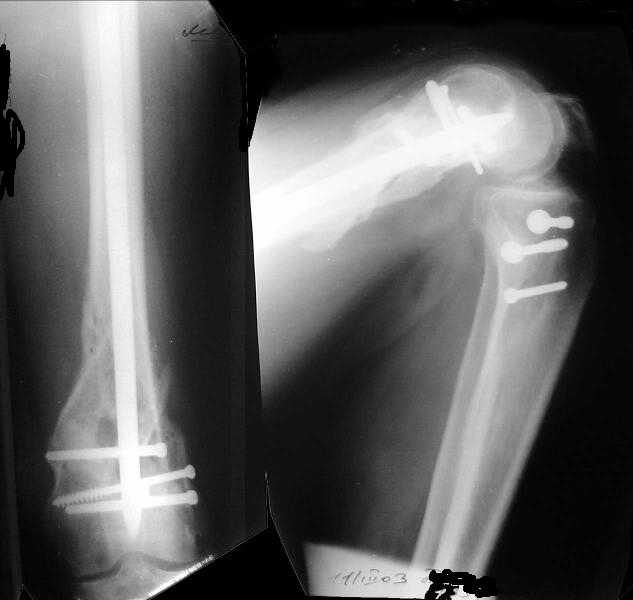

1

2

The mobilisation of knee is started immediately from the second day. Weight bearing is permitted as in any other interlocked nailing. That is, Toe touch to start with and within four days, partial to in another two weeks, full weight bearing. Of course that is assuming that the correct size nail has been used. Up to 70 kg body weight, 11no will be good enough and 12mm if more.Usually at the 1st followup, at 6 weeks time, they have full flexion..I

have seen a few surgeons putting in a drain, but I have not found it unnecessary. There has never been any effusion needing active treatment.

Enclosing a recent intraop picture